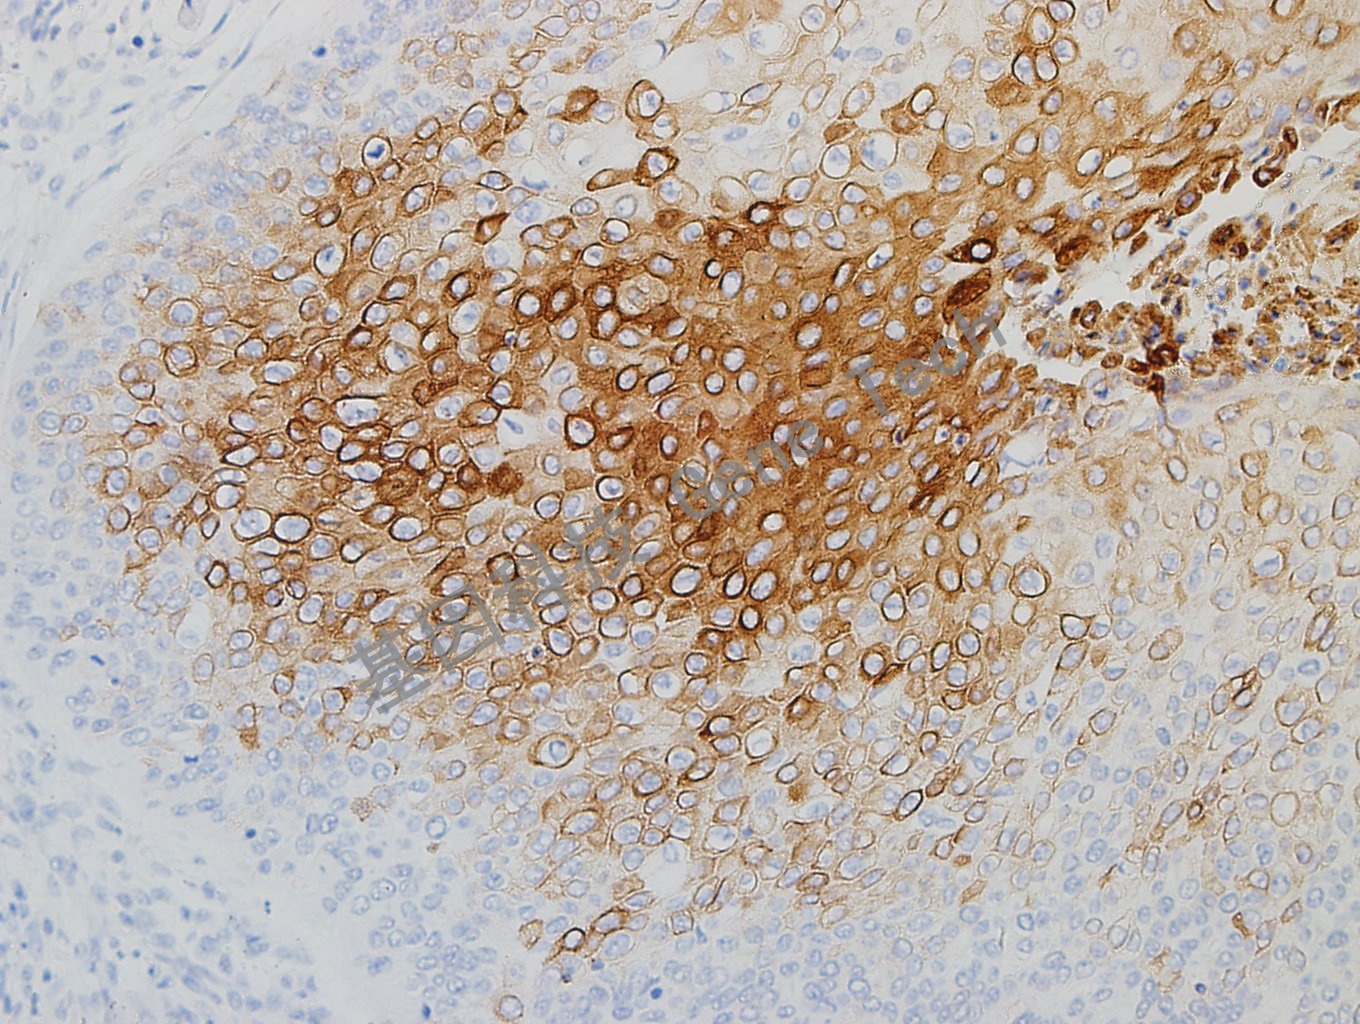

食管癌石蜡切片,用CK10/13(GT2341)染色,细胞浆阳性,DAB显色。